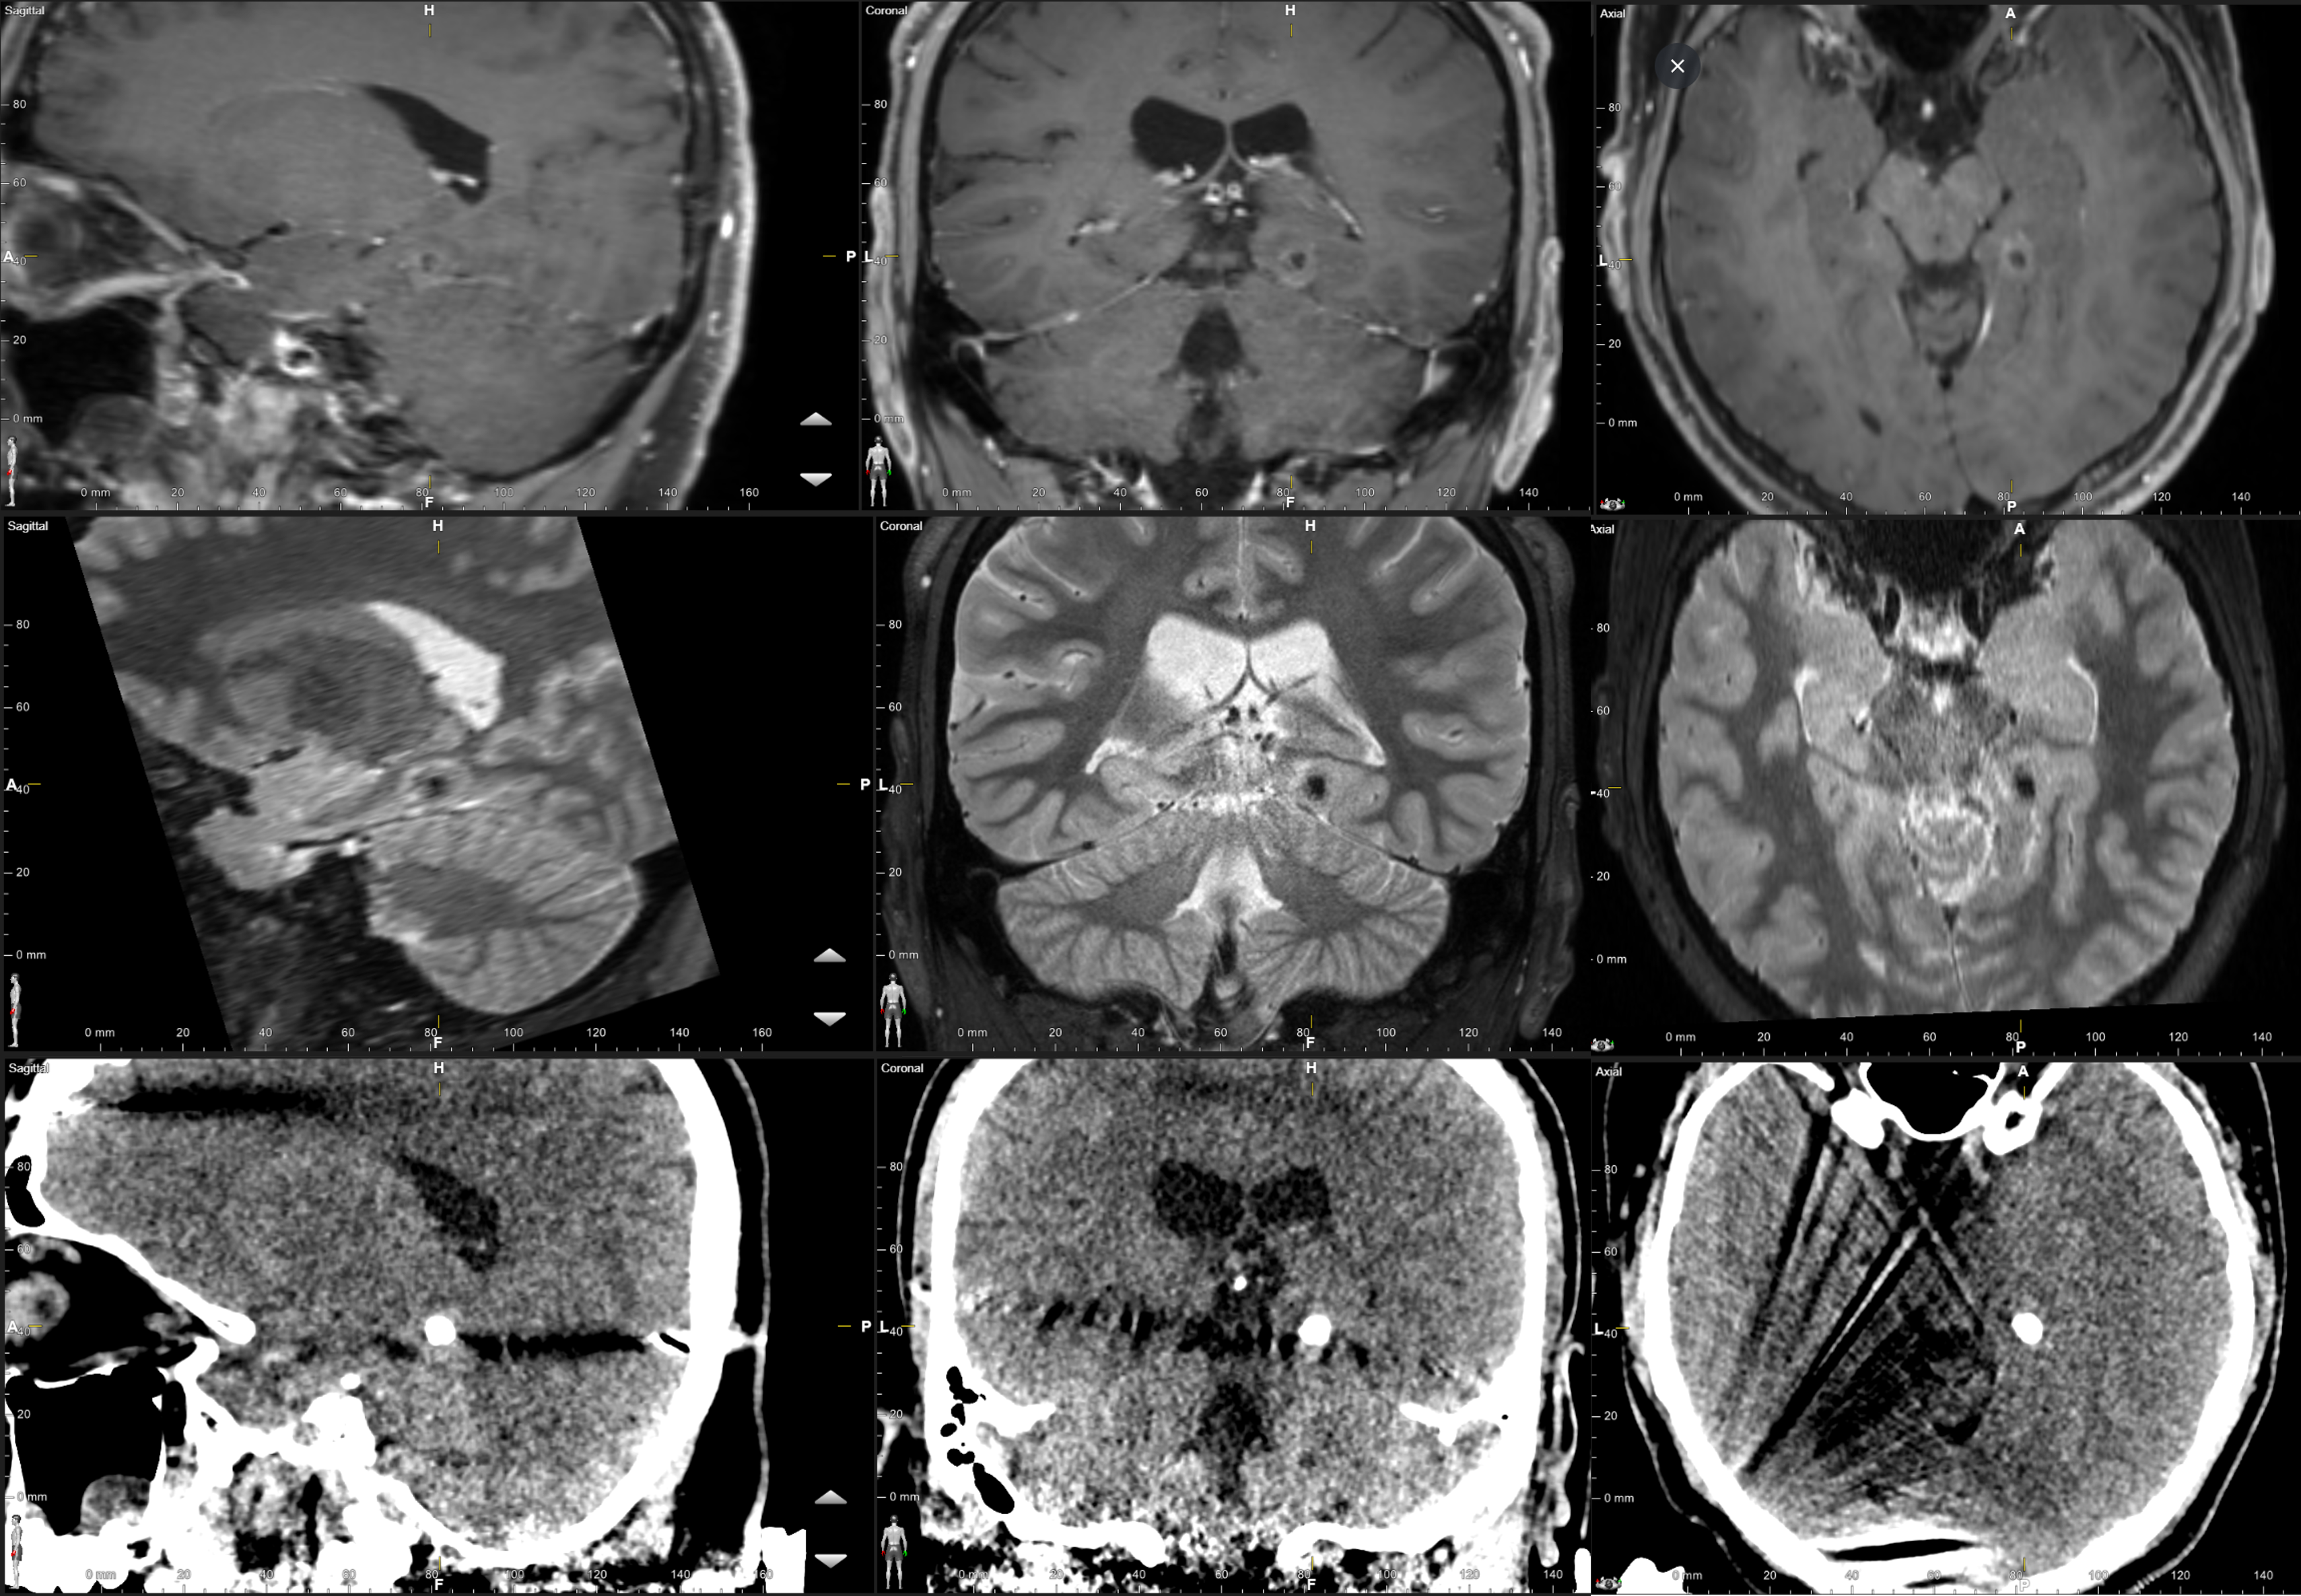

Methods: A 20-25 year old male presented with medically refractory epilepsy with daily focal aware seizures with semiology consisting of episodes of heartburn and a rising sensation that occasionally progressed to brain fog and decreased responsiveness and rare focal impaired awareness seizures. Imaging demonstrated a T2 hypointense, minimally enhancing lesion that was radiographically consistent with a PLNTY tumor in the right posterior parahippocampal/lingual gyrus of the temporal lobe (Figure 1); EEG was concordant with this being the focus of his seizures, with demonstrated maximal right temporal onset. The decision was made to proceed with LITT ablation of this lesion; however, it was noted to be densely calcified on CT imaging (Figure 1). Therefore, two laser filaments were stereotactically positioned to flank the centrally calcified portion of the lesion in the anterior and posterior aspects (Figure 2A). Two laser ablations were then performed, beginning with the anterior trajectory. The two laser filaments were activated to 9.0 Watts ranging from 136 – 143 seconds for treatment.

Results: The thermal ablation zone covered the entirety of the lesion while also demonstrating a thermal shield to the surrounding normal brain parenchyma (Figure 2A). Post-procedure MRI demonstrated peripherally enhancing and overlapping ablation zones within the right posteromedial temporal lobe, which subsumed the calcified mass (Figure 2B). The patient tolerated the procedure well and was discharged on postoperative day 1 without any neurologic or visual field deficits. Follow-up imaging at two months demonstrated a mildly contracted peripherally enhancing ablation zone that continued to encompass the calcified lesion (Figure 2C). The patient has remained seizure free at 6 month follow-up.